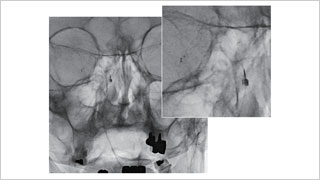

德洲会 名古屋德洲会综合医院 脑神经外科

天野 贵之

脑神经外科

佐藤 俊 先生